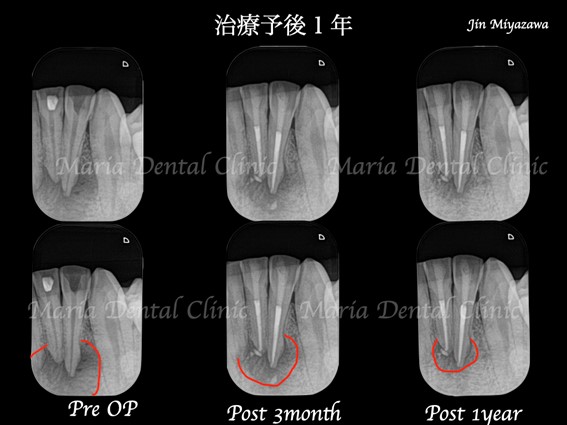

3ヶ月後の経過では歯肉の腫脹、痛みは確認できず、レントゲンでも病変の縮小が確認できたことから1年間隔で経過観察をおこなっております。

術後1年経過し、根尖性歯周炎は治癒傾向を示していることから再度1年後に経過観察を行う予定です。